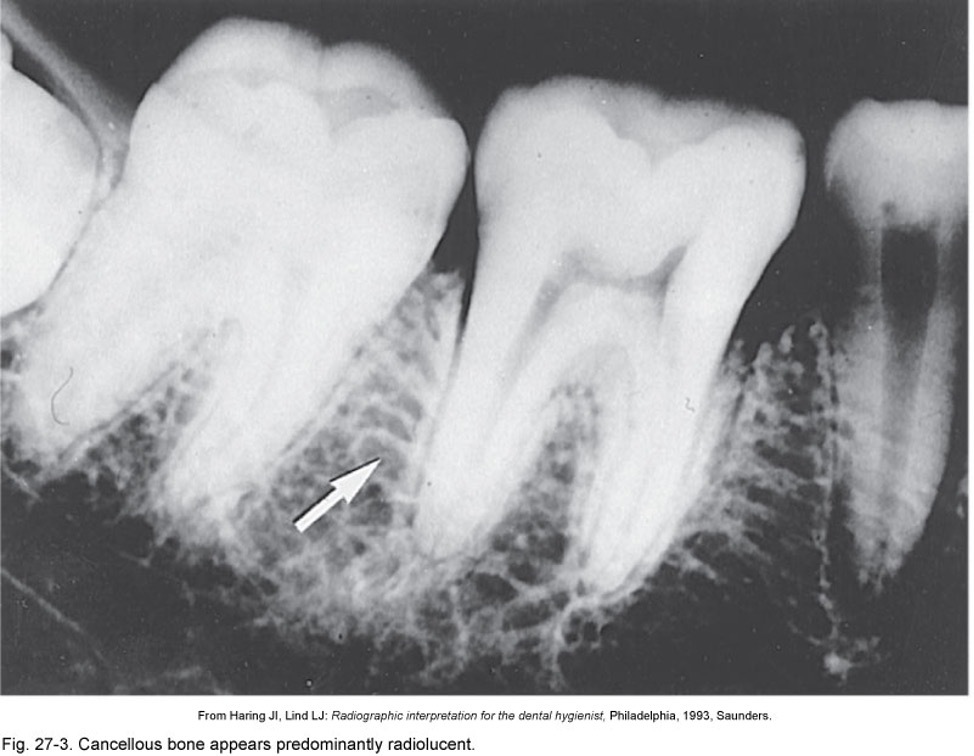

16

Q

What is this a picture of?

A

Cancellous bone

17

Trabeculae (cancellous bone)